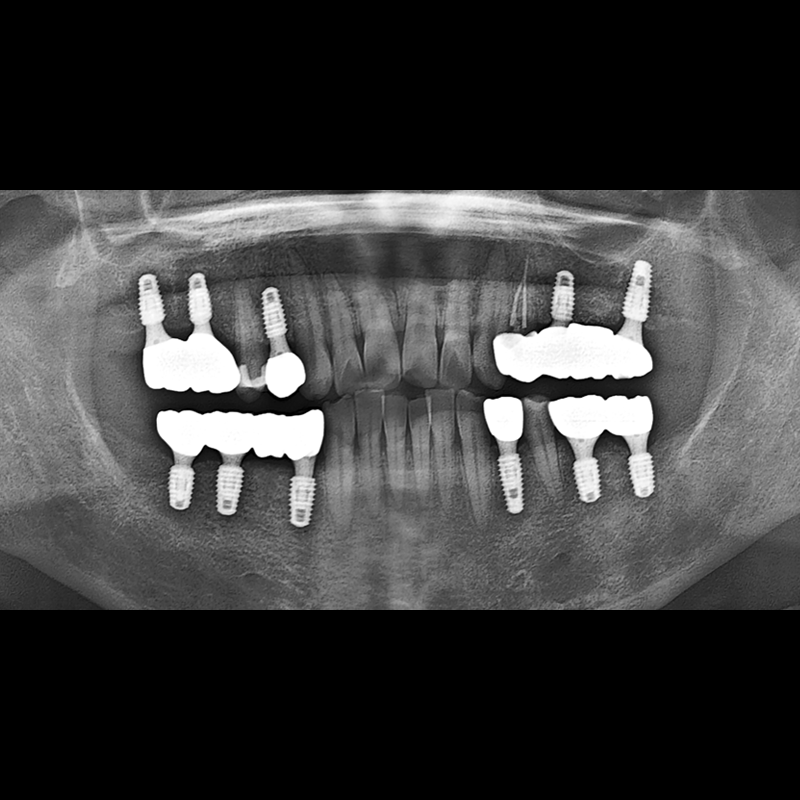

インプラント手術事例 2025.12.10

欠損した歯の部分と、生かしにくい歯の位置にインプラントを植立しました。